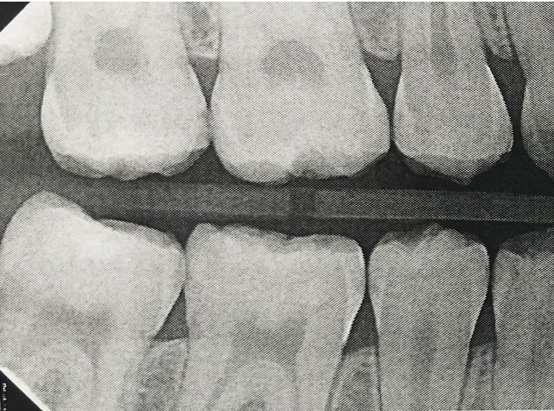

Fig 16. A 15-year-old girl with retained mandibular primary second molar and congenital absence of second premolar (Fig 16). In bitewing film small radiolucencies revealed beginning caries lesions at contact points of primary second molar and adjacent first molar (Fig 17); 12 months later, after initial SDF and 6-month follow-up SDF applications (Fig 18), radiolucencies were not evident.

Fig 17. A 15-year-old girl with retained mandibular primary second molar and congenital absence of second premolar (Fig 16). In bitewing film small radiolucencies revealed beginning caries lesions at contact points of primary second molar and adjacent first molar (Fig 17); 12 months later, after initial SDF and 6-month follow-up SDF applications (Fig 18), radiolucencies were not evident.

Figure 17

Fig 18. A 15-year-old girl with retained mandibular primary second molar and congenital absence of second premolar (Fig 16). In bitewing film small radiolucencies revealed beginning caries lesions at contact points of primary second molar and adjacent first molar (Fig 17); 12 months later, after initial SDF and 6-month follow-up SDF applications (Fig 18), radiolucencies were not evident.

Figure 18